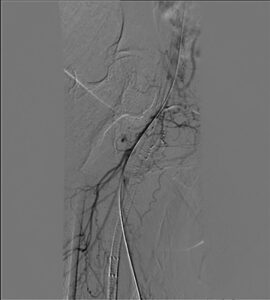

Figure 1. Occluded stent with wire crossing outside the stent

Access was gained in the left common femoral artery. We advanced a 7-frech Pinnacle 65cm sheath up and over to the right CFA. We were able to probe the vessel outside the previously occluded stent and gain access to the true lumen of the vessel beyond the occluded stent in the distal right SFA. A number of wires were used, including stiff Glidewire and an Amplatz wire. The stiff straight guidewire was used, along with a vertebral catheter, QuickCross catheter, and Trailblazer 0.035 catheter. We dilated the vessels with a 3.5mm Nanocross balloon. We then dilated the right superficial femoral artery with a 6mm balloon, followed by a 7mm balloon. After dilation, right SFA occlusion went from 100% to 60% severe recoil. We deployed 6×120 and 6×80 Supera stents, overlapping them with care to improve stacking of the stents to optimize radial strength. This was in the mid to distal SFA. The completion angiogram revealed a good result, with less than 20% residual stenosis at the SFA post double-barrel stenting. Patient tolerated the procedure well and was kept on DAPT.